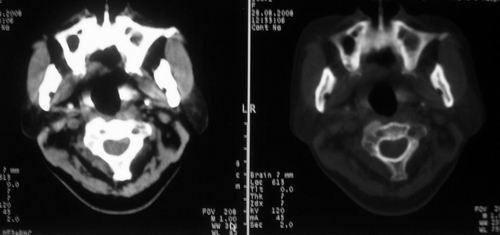

女,55岁,右侧颌下肿物3年。

考虑淋巴结炎[两个];左上颌窦炎性积液

1)考虑右侧颌下腺恶性肿瘤并右侧颈部淋巴结转移。2)左侧上颌窦炎。

鼻咽左侧壁增厚,呈结节样突入鼻咽腔内,左侧咽隐窝消失,须考虑鼻咽癌可能,建议鼻咽纤维镜检查以明确诊断。

至于右侧颌下间隙的结节影,如果不考虑病史的话,可以诊断为淋巴结转移。但是结合病史“右侧颌下肿物3年”,又不象淋巴结转移了。建议ct增强扫描明确结节与右侧颌下腺的关系,或者穿刺活检定性。